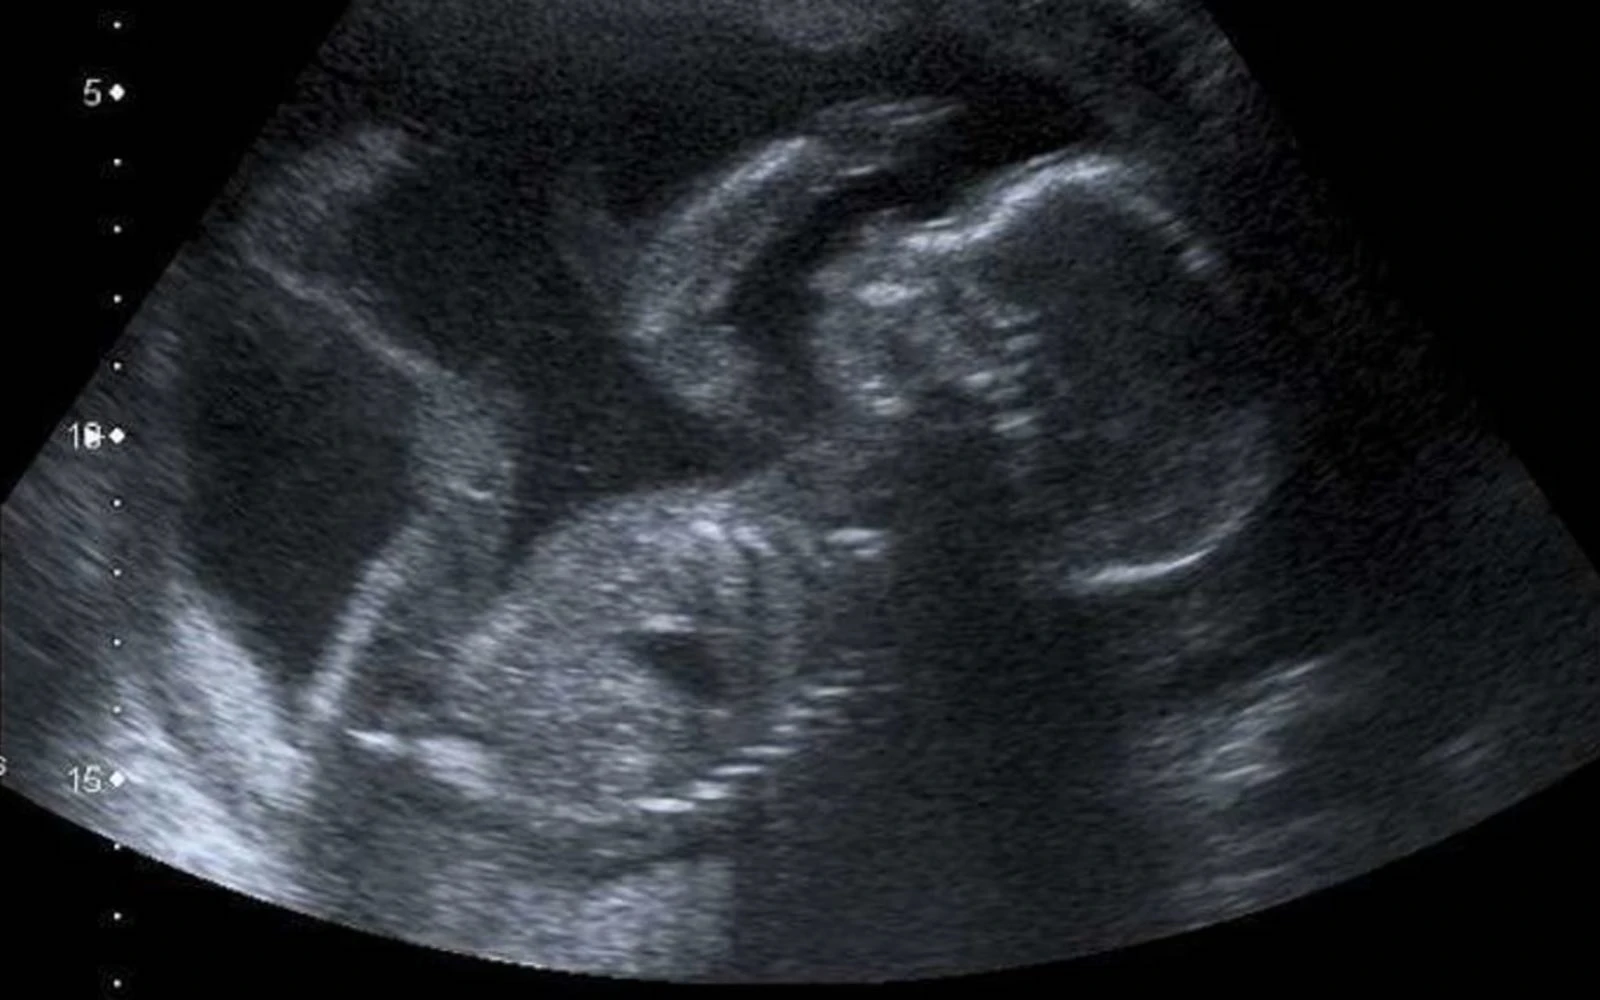

Ultrasonido de un bebé a las 20 semanas de gestación. / Crédito: Steve vía Flickr (CC BY-NC 2.0).